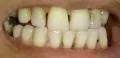

4 месяца назад мне сделали вкладку на предпоследний зуб нижней челюсти, при этом рядом стоящий ближний зуб удалили, т.к. было нагноение на десне. Я не сделала коронку на один зуб, т.к. хотела закрыть просвет и от недостающего зуба. Но и стачивать ближний зуб (здоровый) мне не хотелось. На дорогой имплант средств не нашлось. Сейчас зуб со вкладкой стал побаливать и на десне снова появилось нагноение. Из-за чего это произошло и что мне теперь делать? Явилось ли моё промедление результатом нагноения или это могло произойти и под коронкой?